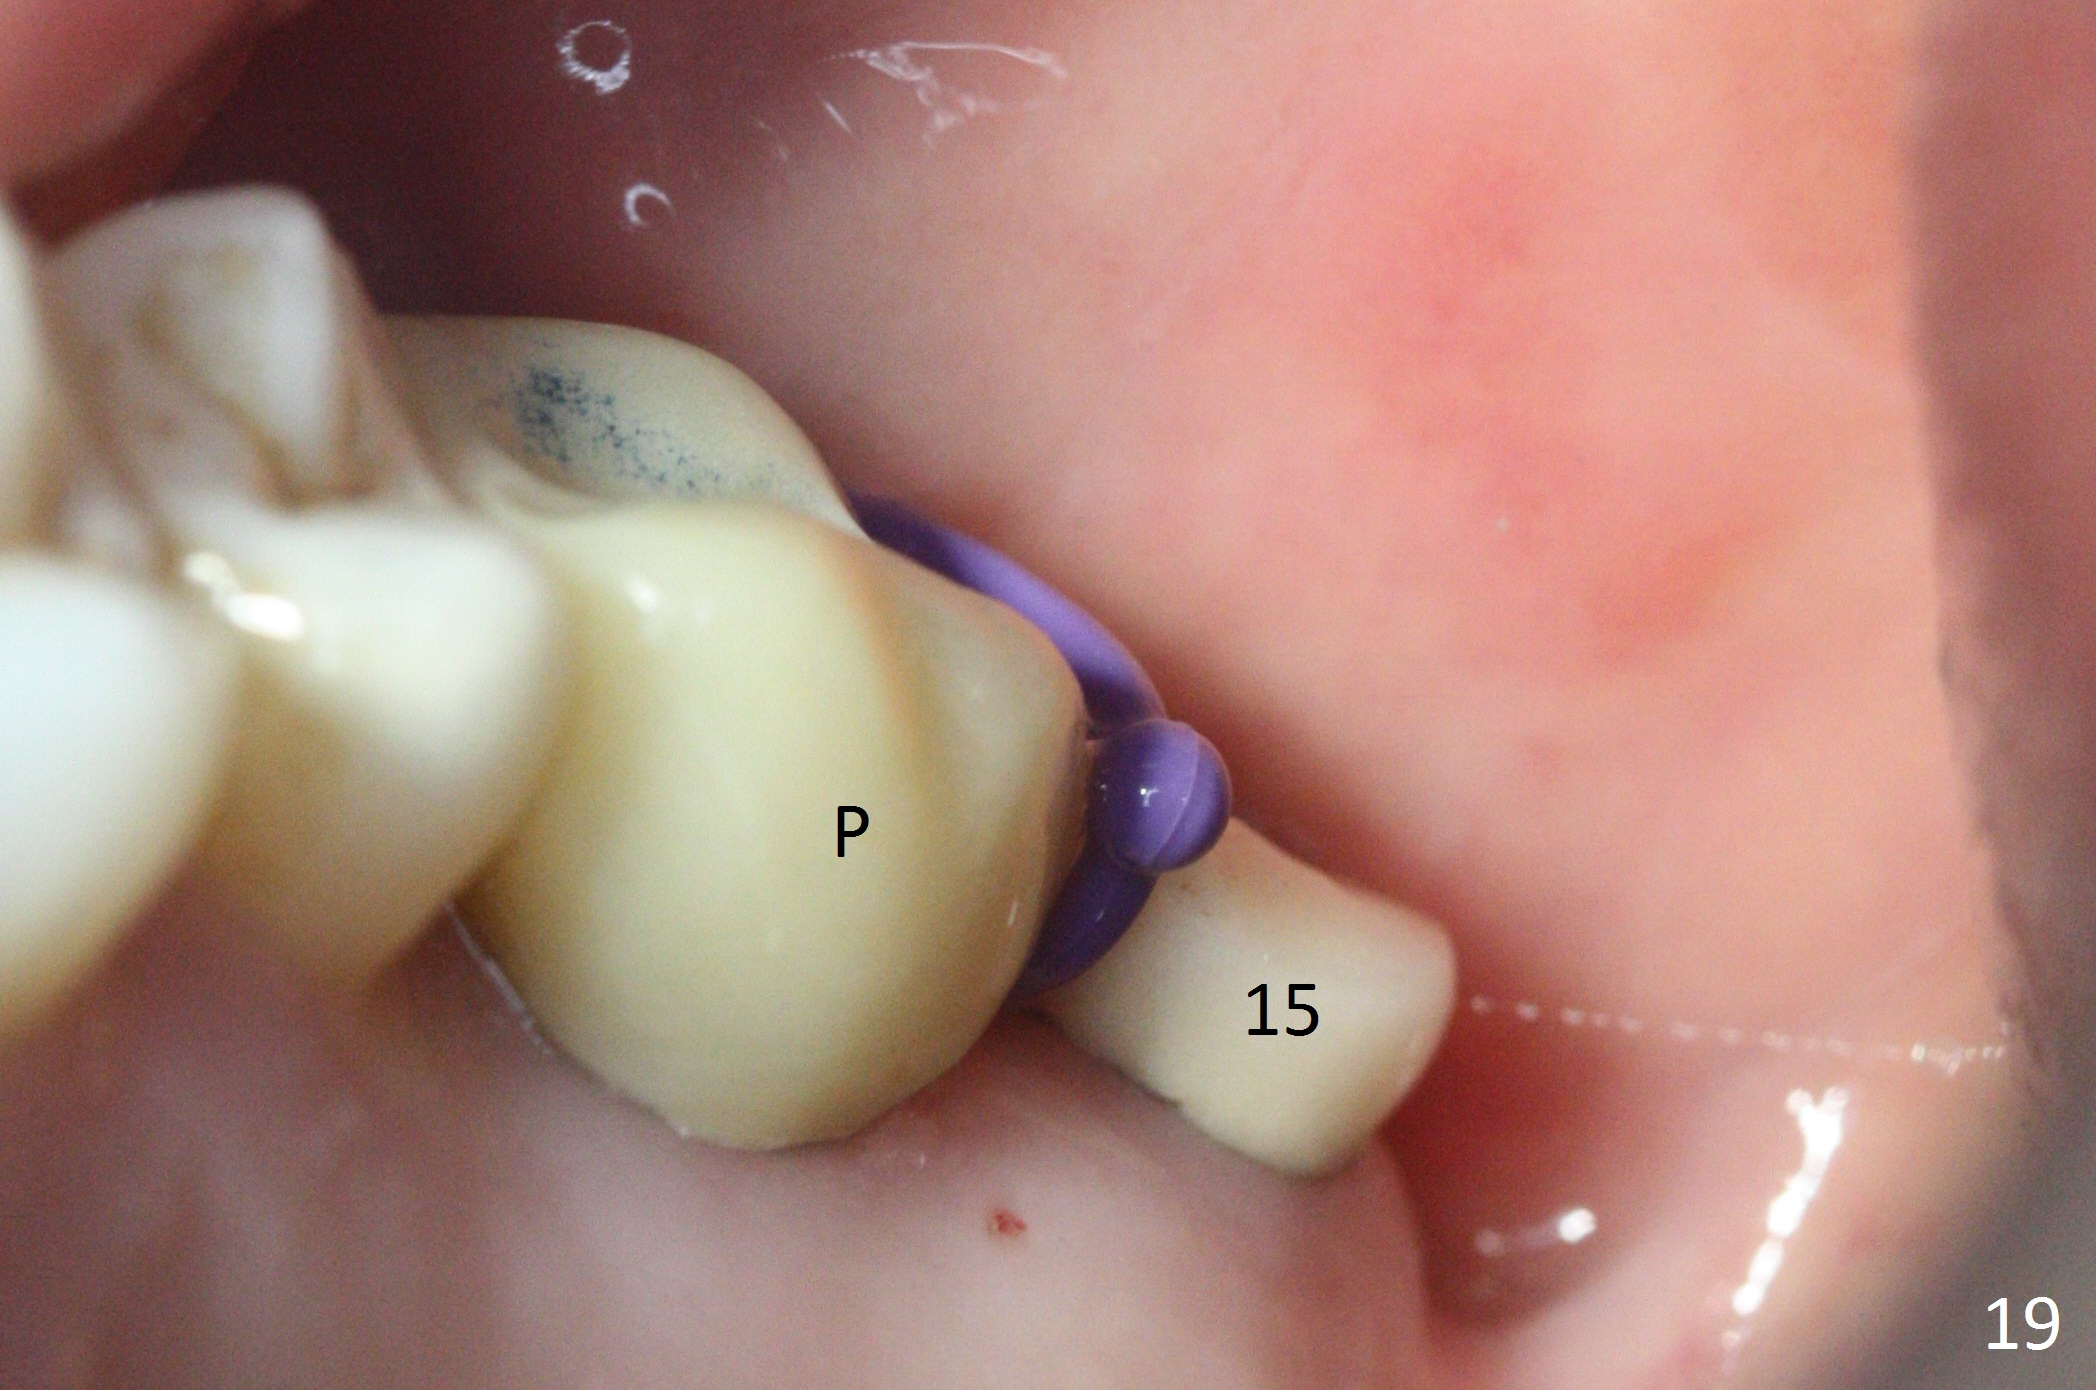

The implant is stable 8 months postop (Fig.15). When a 6x4(3) mm abutment is placed 8.5 months postop, it is distal (Fig.16). The mesiodistal width is 1-2 mm shorter than that at #3, which suggests the mesial shift of the tooth #15. A provisional is fabricated at #14 (Fig.17 P) with supra-occlusion so that there is clearance between the tooth #15 and the opposing one (Fig.18 *). With a separator placed between #14 and 15 (Fig.19), the latter is free to be distalized. Bone volume and density seem to increase 4.5 and 10.5 months post cementation (Fig.20,21, as compared to Fig.15), although the buccal plate remains as concave as shown in Fig.18. One year 5 months post cementation, the patient complains of bad smell from the implant when water pik is being used. It appears that the 1st 2-3 threads are exposed (Fig.22), although the surrounding gingiva remains uninfected. Bone graft is recommended. The site heals without bad smell 7 months post bone graft (2 years 4 months post cementation, Fig.23). The 1st implant thread is found exposed buccal on uncover (regraft?). A small healing abutment is placed because the implant is placed distal (Fig.24). An angled abutment should be tried and #15 crown will be redone. Impression will be taken when the gingiva heals around the provisional crowns.